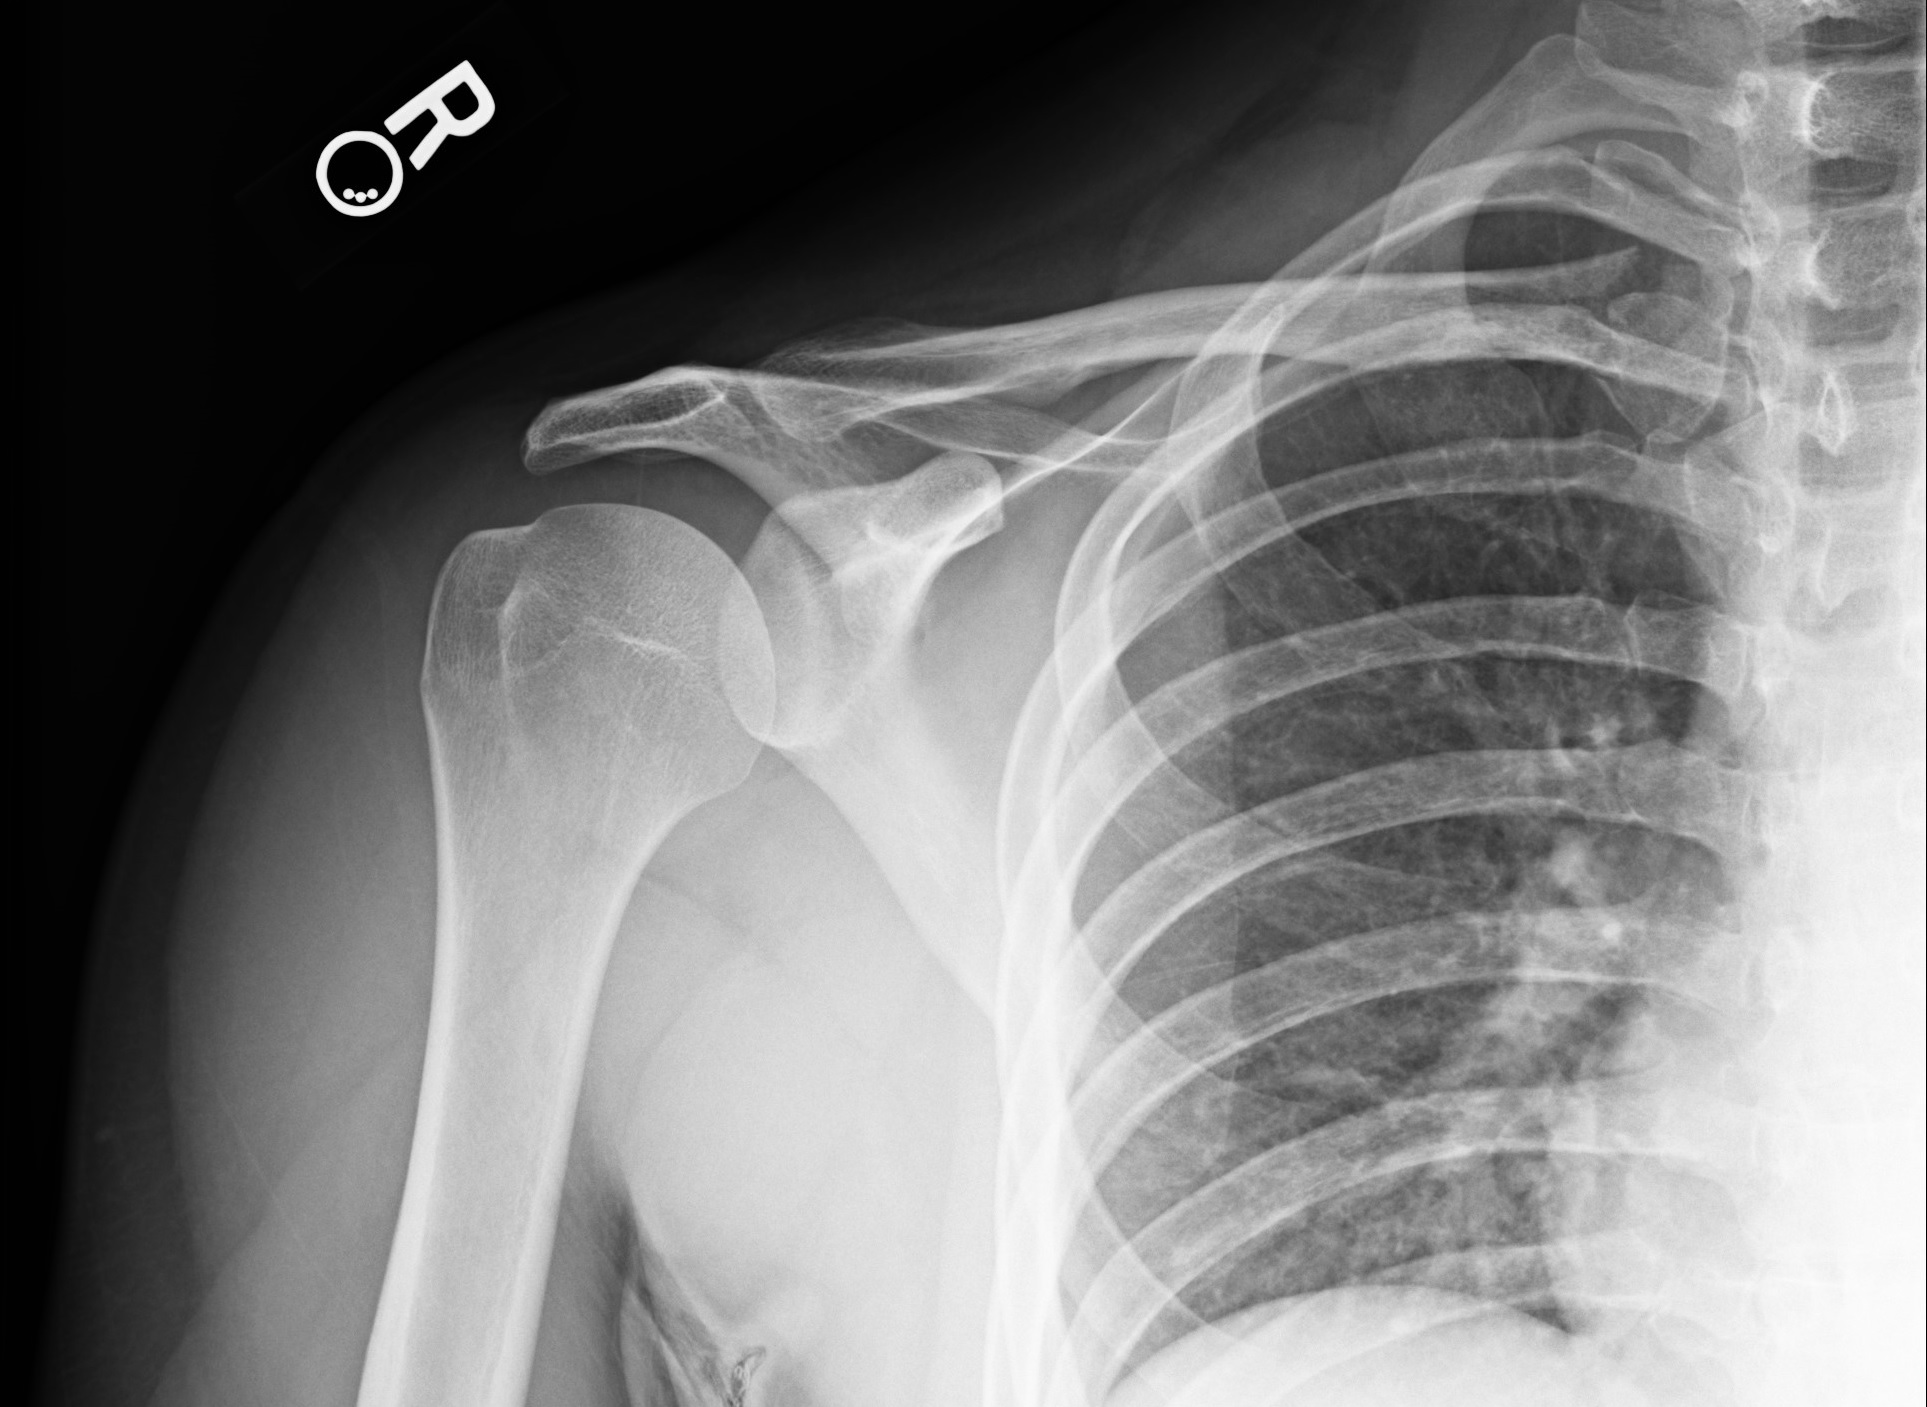

Radiographs of the right shoulder were taken (Figures 1-3).

Figure 2. Anteroposterior view of right shoulder, external rotation.